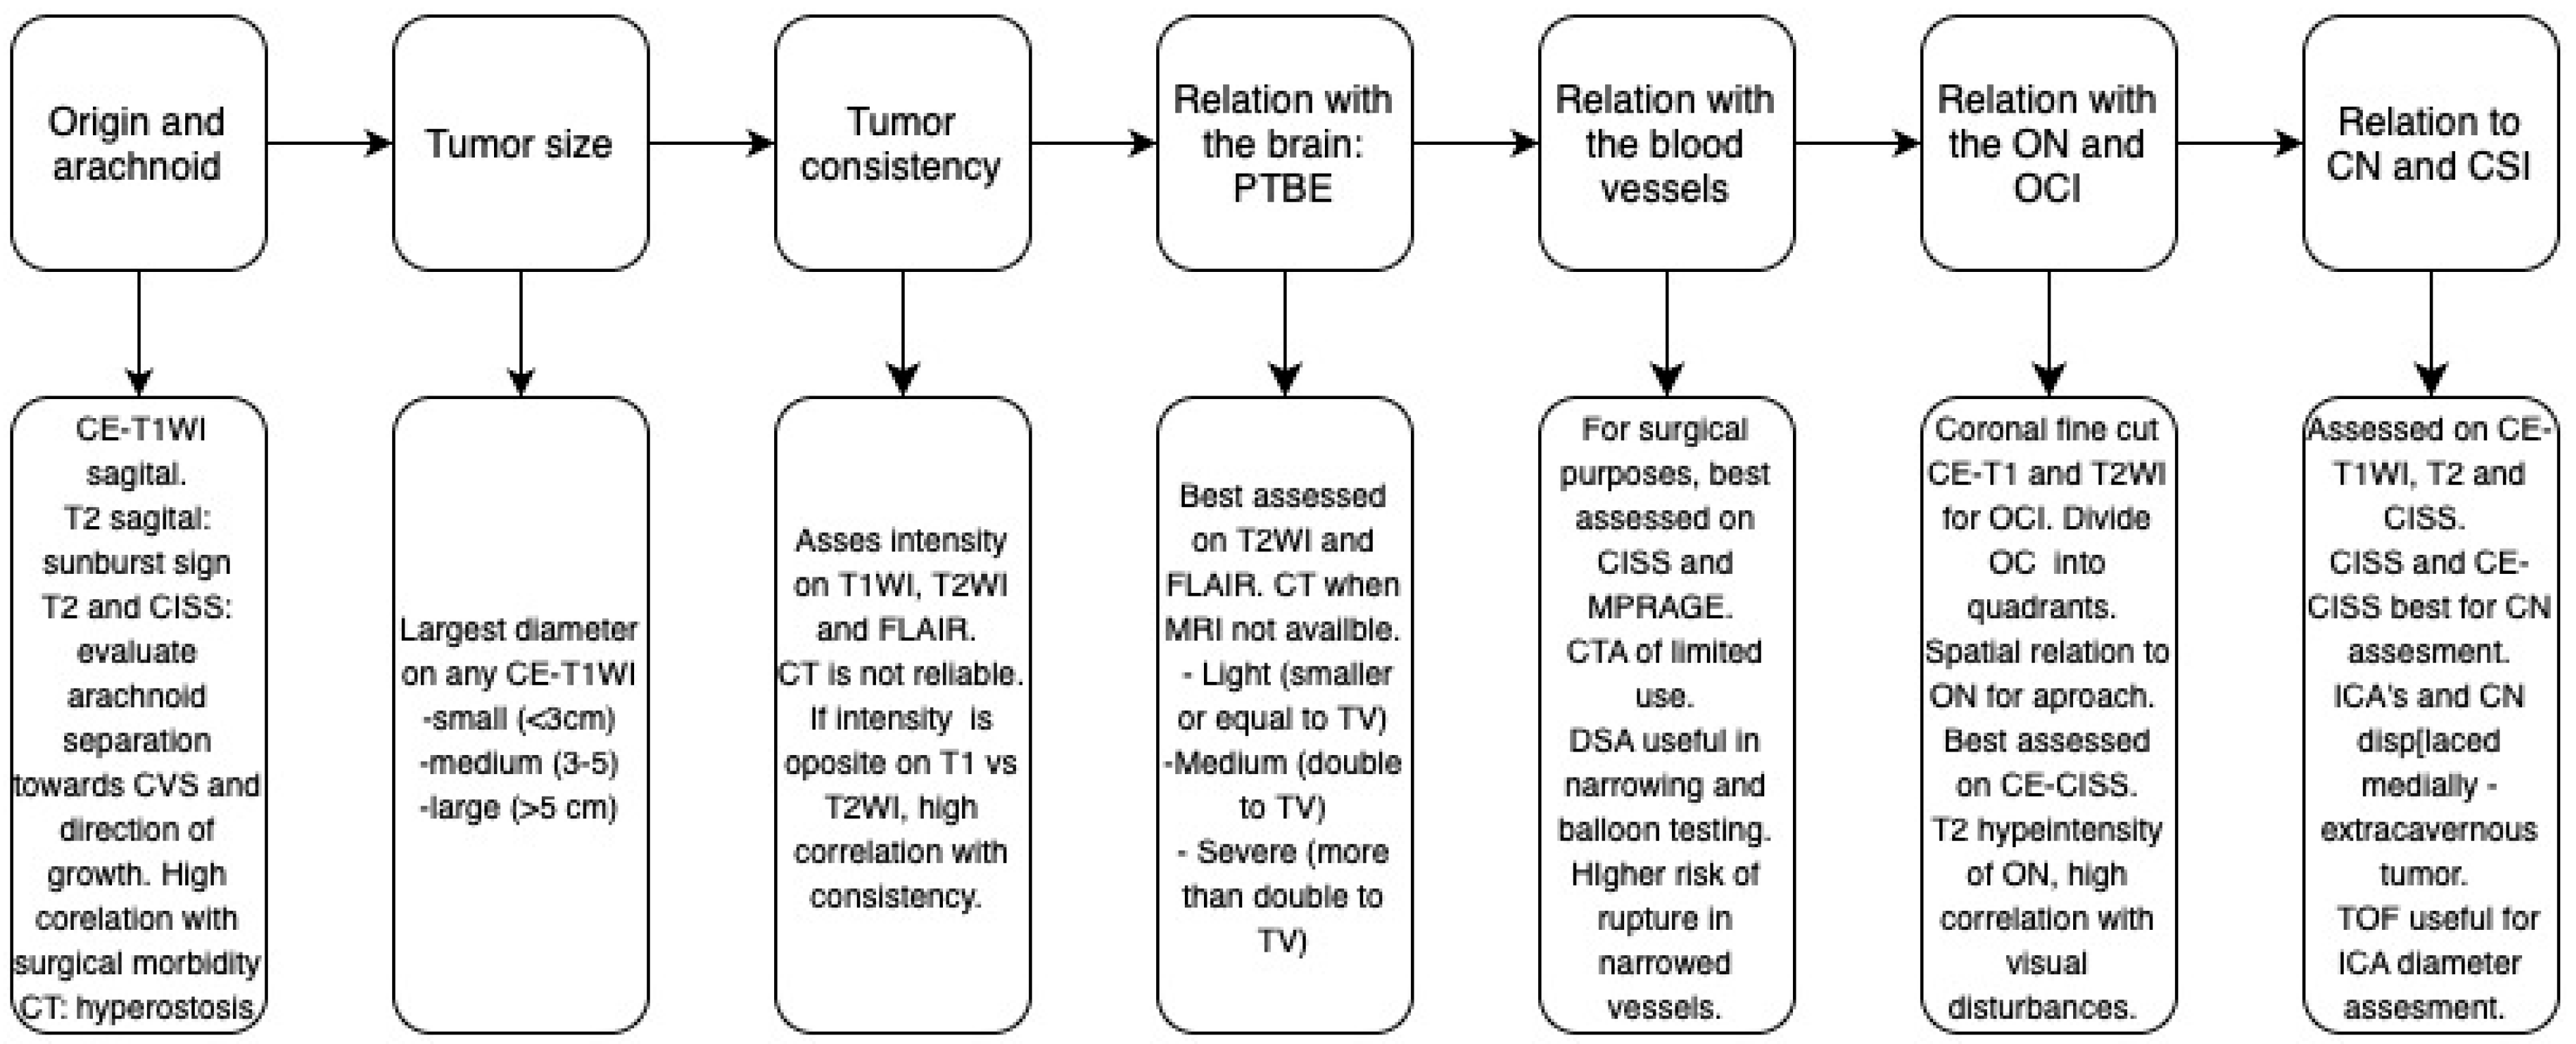

2. Assessment of Tumor Origin and the Presence of an Arachnoid Cleavage Plane

2.2. Imaging Evaluation

3. Tumor Size

3.2. Imaging Evaluation

4. Assessment of Tumor Consistency

4.2. Imaging Evaluation

5. Assessment of Peritumoral Brain Edema (PTBE)

5.2. Imaging Evaluation

6. Vascular Encasement

6.2. Imaging Evaluation

7. Optic Canal Involvement (OCI) and Optic Nerve (ON) Compression

7.2. Imaging Evaluation

8. Cavernous Sinus Involvement (CSI)

8.2. Imaging Evaluation